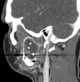

Unerupted tooth

Dentigerous cyst, also known as follicular cyst is an epithelial-lined developmental cyst formed by accumulation of fluid between the reduced enamel epithelium and crown of an unerupted tooth. It is formed when there is an alteration in the reduced enamel epithelium and encloses the crown of an unerupted tooth at the cemento-enamel junction. [Source: Wikipedia ]